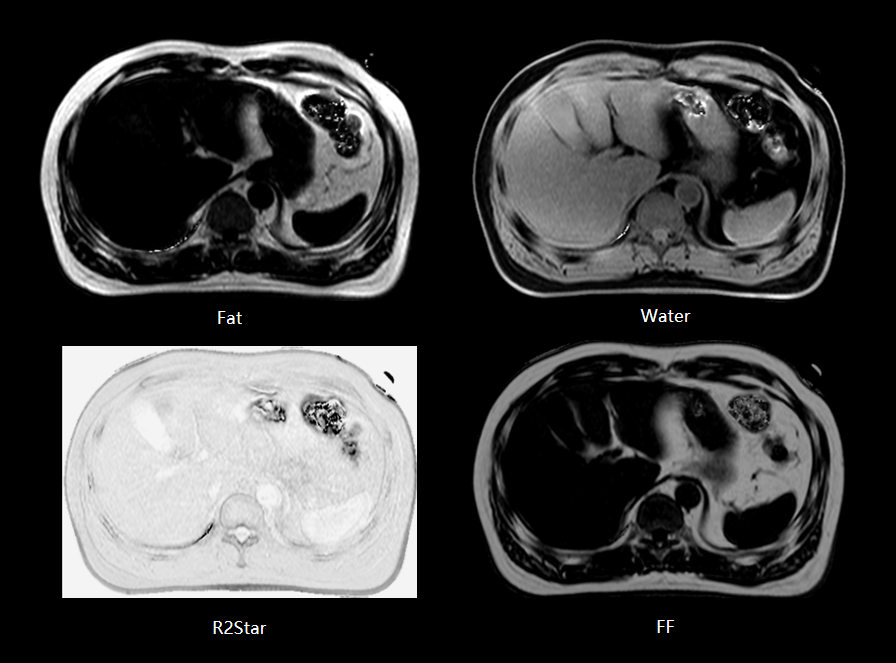

FACT 脂肪定量成像